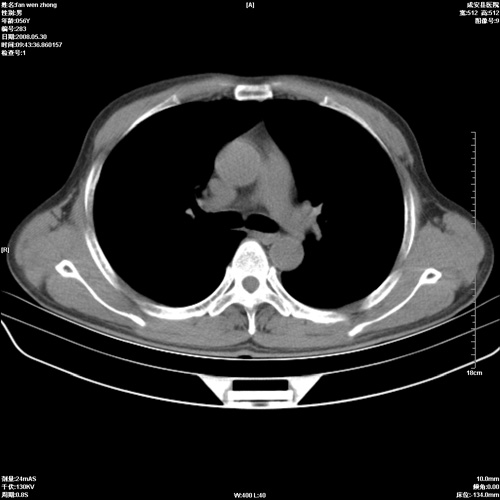

病人 男 56岁 一周前高热,体温达39-40度,经抗炎治疗后,体温渐降,达37,5-38度,轻微咳嗽,胸部不适 查白细胞为1.3万 行ct检查,请分析。

双肺内可见多发结节状病灶,并见小空洞,病人高热,白血球增高,应该是典型的迁徙性肺脓肿(多为金黄色葡萄球菌感染)。查一下口腔等其它部位有无感染灶。

双肺内可见多发结节状病灶,并见小空洞,病人高热,白血球增高,应该是典型的迁徙性肺脓肿(多为金黄色葡萄球菌感染)。建议治疗后复查.